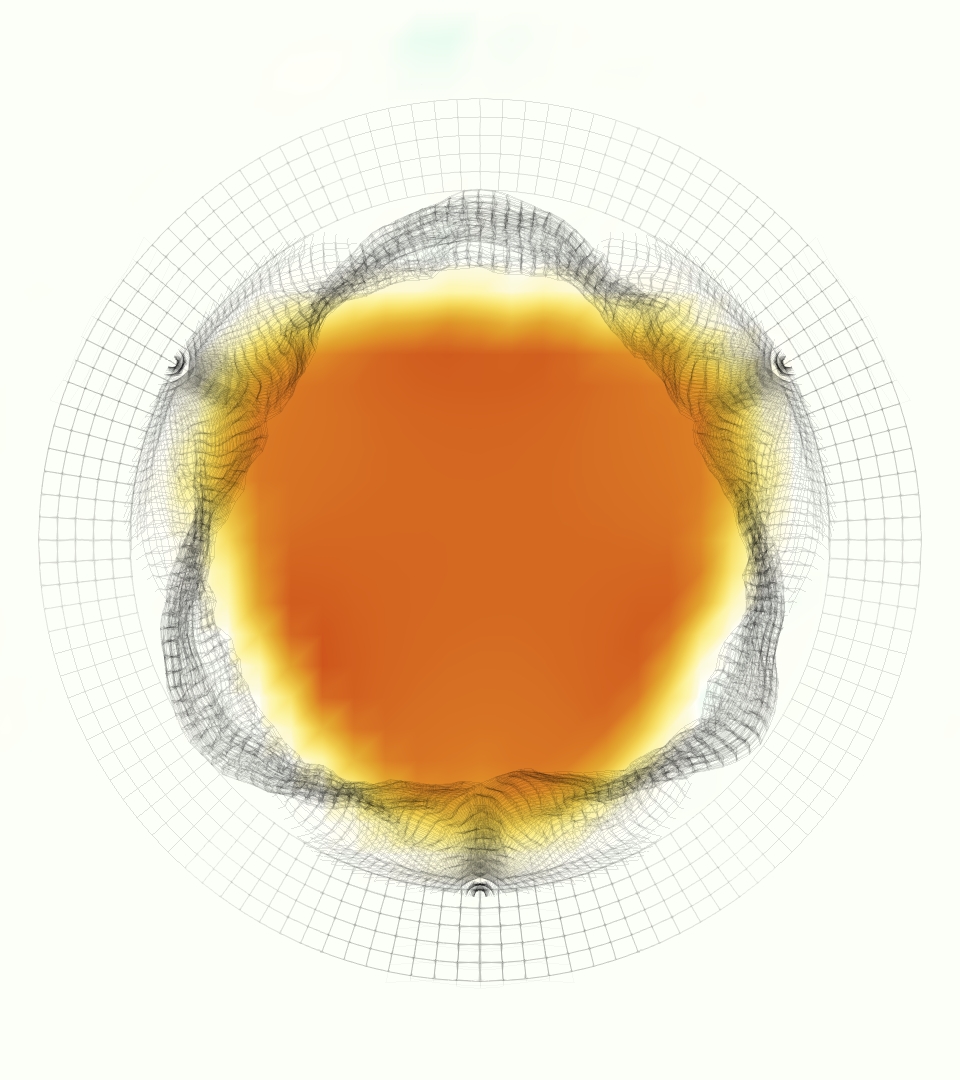

The phase-averaged, resampled velocity fields during peak systole and flow rates at each resolution are shown in Figure 10. Despite the limitations discussed above, we observe similar qualitative trends in the flow field at all resolutions. At all resolutions, a jet formed and angled up downstream of the valve orifice, as shown in the sagittal view. The jets showed a triangle-like cross section at with points aligned with the commissures. At cm, the jet appears like a rounded triangle in the opposing orientation, with its points aligned with the center of the leaflets. At cm, the jet is narrower downstream of the commissures, and wider downstream of the leaflets, again with a triangle-like cross section. The area of the jet increased with resolution, as expected given the IB method thickening of the valve structure. The narrowed jets at the two more coarse resolutions show locally elevated velocities relative to the two more fine resolutions. Figure 11 shows the instantaneous velocity fields at each resolution in the same axial and sagittal views. At 0.9 mm, the sagittal view shows a qualitatively different jet than at finer resolutions, with regions of lower velocity farther from the vessel wall, indicating insufficient resolution. At 0.9 and 0.68 mm, the jet is visibly narrowed compared to higher resolutions. While some features are similar at these two coarse resolutions, we conclude that the narrower jets indicate these simulations are under-resolved. Flows in the three finest resolutions, 0.45, 0.34 and 0.28 mm. appeared qualitatively similar, with slightly more fine structure detail in both the axial and sagittal views present at the edges of the jet. The jets in the axial views all showed a similar triangle-like cross section, slightly narrower downstream of the commissures, as in the phase-averaged fields. In both the phase-averaged and instantaneous fields, the three finest resolutions appear sufficiently similar that the conclusions of this study would be identical with any of these resolutions.

Figure 13 shows the integral metric evaluated at cm with various resolutions, where each resolution uses its own velocity scale (see eqn. (18)). Values at 0.9, 0.68 were elevated relative to finer resolutions, indicating under resolution. Values of at 0.45, 0.34 and 0.28 mm are extremely similar, with slight decrease as resolution increases. Values of at 0.625 and 1.25 cm showed similar trends and are not shown.